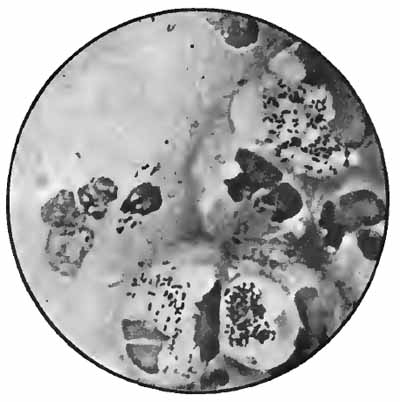

Sputum from a case of actinomycosis

FIG. 8.—Sputum from a case of actinomycosis; stained (Jakob).

5. Actinomyces Bovis (Ray-fungus).—In the sputum of pulmonary actinomycosis and in the pus from actinomycotic lesions elsewhere small, yellowish, "sulphur" granules can be detected with the unaided eye. The fungus can be seen by crushing one of these granules between slide and cover, and examining with a low power. It consists of a network of threads having a more or less radial arrangement, those at the periphery presenting club-shaped extremities (Fig. 8). This organism, also called Streptothrix actinomyces, apparently stands midway between the bacteria and the molds. It stains by Gram's method.

[p. 32] Actinomycosis of the lung is rare. The clinical picture is that of tuberculosis.